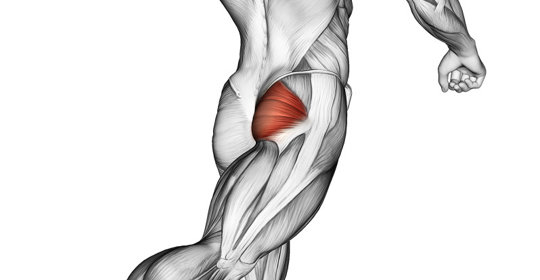

嬰兒腳內彎:原因、判斷及醫治